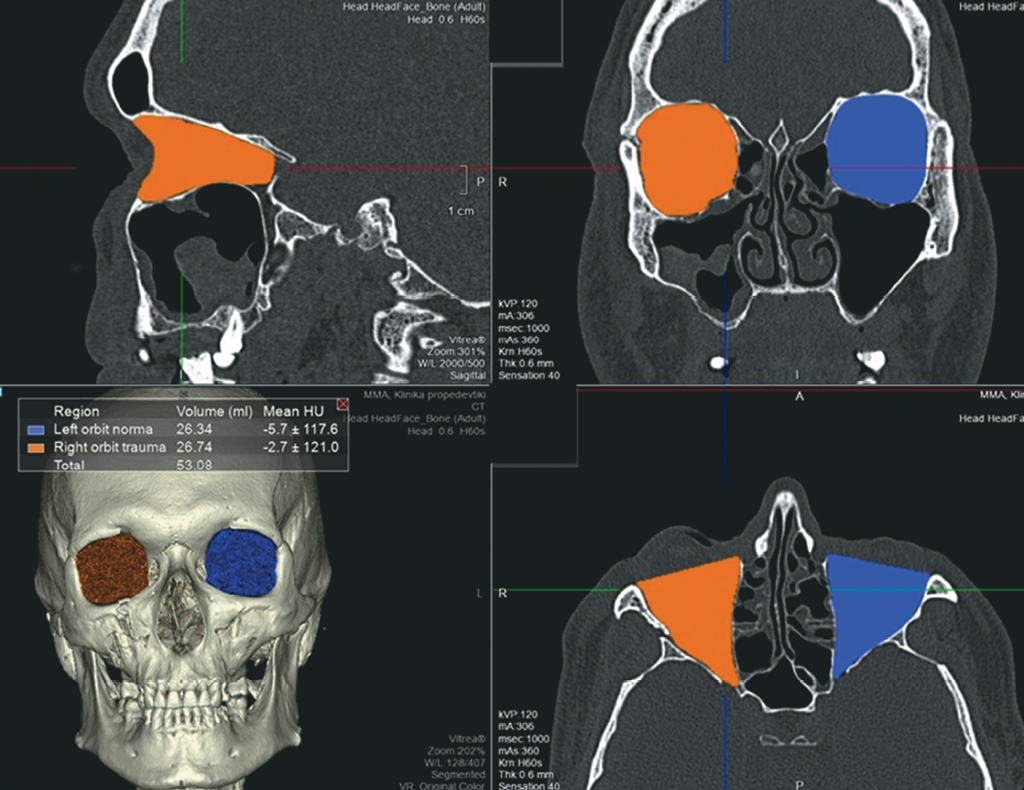

В рамках динамического обследования пациенту была проведена МСКТ через 2 года после получения травмы. На изображениях отмечается восстановление костных стенок правой орбиты, а также восстановление стенок правого верхнечелюстного синуса и скуловой дуги, при этом визуализируется деформация латеральной стенки синуса (рис. 6). Пролабирования мягких тканей правой орбиты в верхнечелюстной синус не определяли.

Рис. 6. МСКТ, средняя зона лица, костный режим. Коронарная (a), аксиальная (b, c) и сагиттальная (d) реконструкции. На полученных изображениях отмечается восстановление костных стенок правой орбиты, а также восстановление стенок правого верхнечелюстного синуса и скуловой дуги, при этом визуализируется деформация латеральной стенки синуса. Пролабирования мягких тканей правой орбиты в верхнечелюстной синус не определяется

Fig. 6. MSCT, midface, bone window. Coronal (a), axial (b, c), and sagittal (d) reconstructions. On obtained images, there is a bony walls’ repair of the right orbit, as well as of those of right maxillary sinus and of zygomatic arch; at the same time there is a deformation of maxillary sinus lateral wall. There is no herniation of right orbit soft tissues into the maxillary sinus

Для оценки изменения объёма правой орбиты нами была применена методика расчёта объёмов орбиты с помощью обработки МСКТ-изображений на рабочей станции (рис. 7). В позднем посттравматическом периоде разница объёмов травмированной и здоровой сторон составила 0,67 мл, что находится в диапазоне допустимых значений и свидетельствует о минимальном риске развития энофтальма.

Рис. 7. МСКТ, средняя зона лица, костный режим. Измерение объёмов орбит после травмы на рабочей станции. Измерение объёмов орбит через 2 года после травмы. В позднем посттравматическом периоде разница объёмов травмированной и здоровой сторон составила 0,67 мл

Fig. 7. MSCT, midface, bone window. Orbital volume assessment after trauma at a workstation 2 years after trauma. In the late post-traumatic period, the volume difference between the affected and the normal side was 0.67 ml